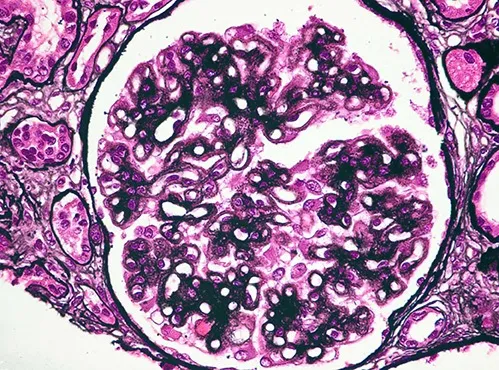

A Nefropatia Membranosa (NM) é uma das formas mais prevalentes de glomerulopatia com síndrome nefrótica em todo o mundo.

Sabemos que a terapia imunossupressora é fundamental para pacientes que apresentam NM com proteinúria nefrótica persistente, queda na taxa de filtração glomerular e para aqueles com altos títulos de anticorpos contra o receptor da fosfolipase A2 (anticorpo anti-PLa2r).

Estes últimos são considerados pacientes de maior risco de progressão para DRC avançada e estão mais sujeitos a complicações trombóticas.